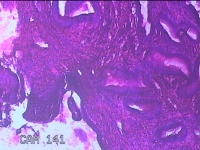

宫颈7点组织 宫颈12点组织

性别

女

年龄

44岁

临床诊断

一般病史

宫颈筛查高危型hpv51阳性

标本名称

大体所见

1.“宫颈7点组织”:灰白粉红色组织0.7x0.3x0.2cm一块。 2.“宫颈12点组织”:灰白粉红色组织0.8x0.7x0.2cm两块。